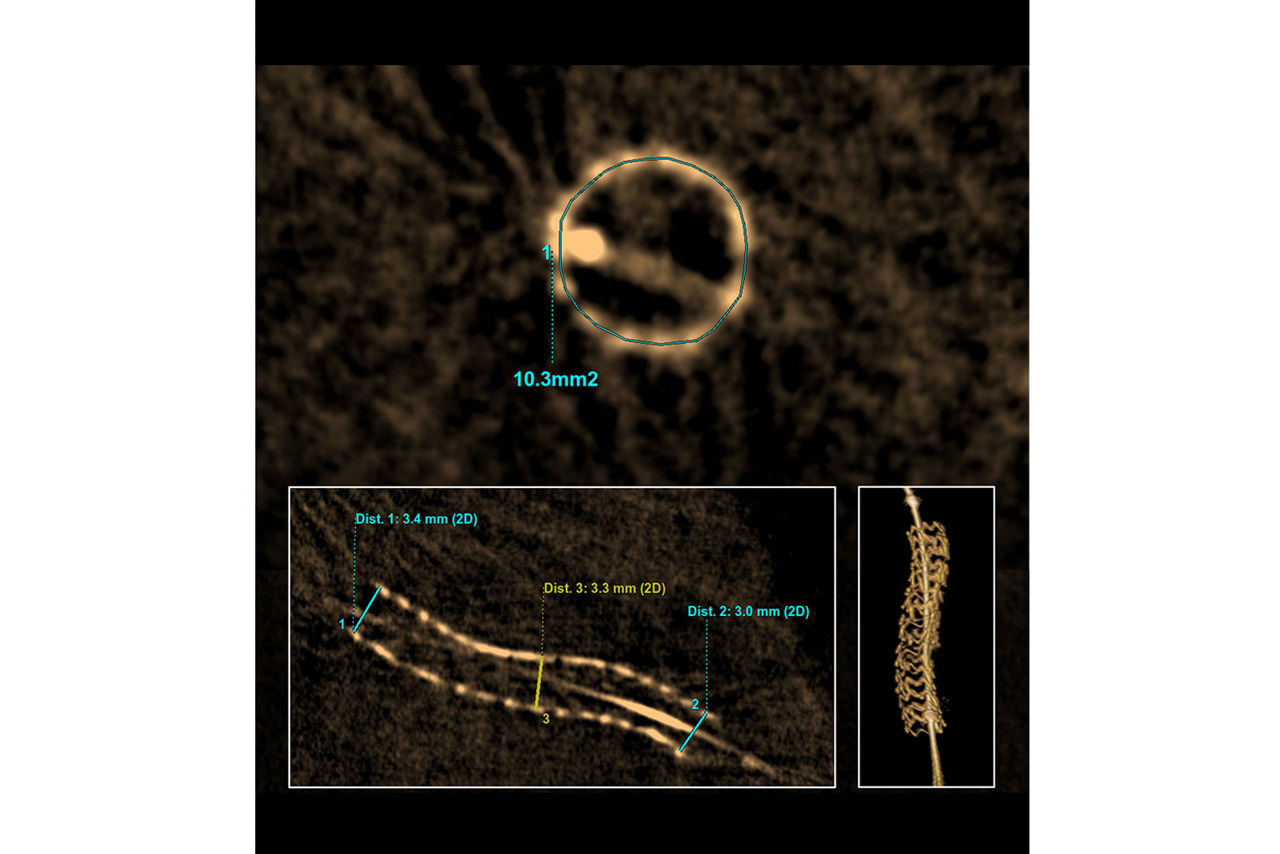

EASY image interpretation and FAST measurements

Intuitive images and straightforward user interface designed for fast area and diameter measurements on stent reconstruction.

In imaging, it is sometimes challenging to understand and analyze the different elements shown on the screen. 3DStent images are intuitive and easy to understand. Simple images diminish the learning curve and allows for faster image interpretation.

In a couple of clicks, get all the information you want like diameters and cross sectional areas.